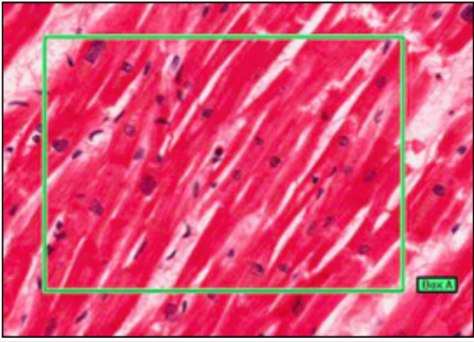

CARDIAC MUSCLE (MYOCARDIUM)

- branching chains of cardiac myocytes

- striations (myofibrils and repeat sarcolemmas)

- dark intercalated discks (myocyte junctions)

differ from skeletal -

- structural - branched, mononuclear (central), no stem cells

- physiological - contract/relax without rest, secrete hormones (ANP- when stretched excessibely, increases water/Na+/K+ excretion, inhibits RAAS)